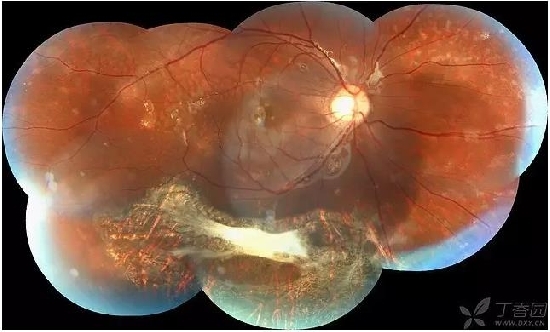

患者,女,双眼黄斑裂孔伴网膜脱离,双眼高度近视。右眼因为有白内障,眼底照相不清楚,没发上来